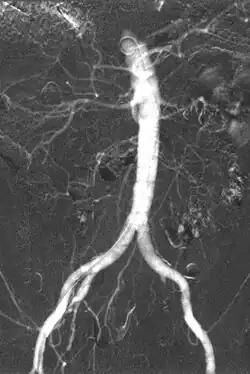

- Angiography (arterial investigations)

Iodinated contrast contains iodine. It is the main type of radiocontrast used for intravenous administration. Iodine has a particular advantage as a contrast agent for radiography because its innermost electron ("k-shell") binding energy is 33.2 keV, similar to the average energy of x-rays used in diagnostic radiography. When the incident x-ray energy is closer to the k-edge of the atom it encounters, photoelectric absorption is more likely to occur. Its uses include: